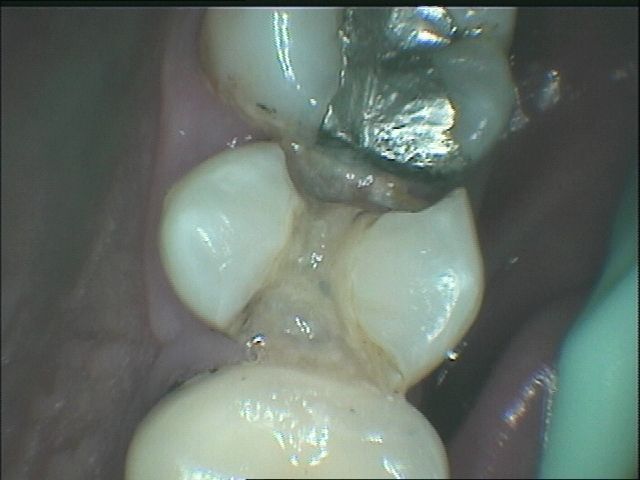

牙縫是一般患者發生蛀牙最易忽略的地方,因為難以被看見

初期蛀牙,可以採取樹酯填補,如以下步驟:

但是樹酯因為強度不足往往一段時間後,產生邊緣龜裂,與二次蛀牙這時候蛀牙範圍往往會比第一次更大,可以使用3D齒雕作修復, 提供牙齒良好的強度與美觀。